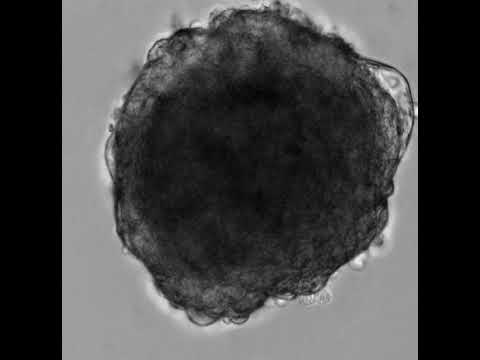

Ein Schwerpunkt unserer Stammzellforschung liegt auf der translationalen Erforschung des Herzens. Dafür nutzen wir adherente Zellkultursysteme basierend auf Herzmuskelzellen aber auch komplexere, multizelluläre 3D-Herzorganoide.

In funktionellen Assays lassen sich unter anderem Kontraktionsverhalten und weitere wichtige physiologische Parameter analysieren. Mit diesen Plattformen können Herzerkrankungen wie Hypertrophie oder ein Myokardinfarkt nachgebildet werden, um die Wirksamkeit neuer Therapieansätze zu testen. Zusätzlich können Sicherheitsparameter erfasst und potenzielle Nebenwirkungen auf das Herz bewertet werden – ein wichtiger Beitrag zur sicheren Entwicklung neuer Medikamente.

Herzorganoide sind dreidimensionale Gewebsmodelle, die zentrale strukturelle und funktionelle Eigenschaften des menschlichen Herzens abbilden und damit klassische zweidimensionale Zellkulturansätze deutlich erweitern.

Die räumliche Organisation unterschiedlicher Zelltypen ermöglicht eine physiologisch relevantere Testplattform und verbessert so die Aussagekraft translationaler Forschungsansätze.